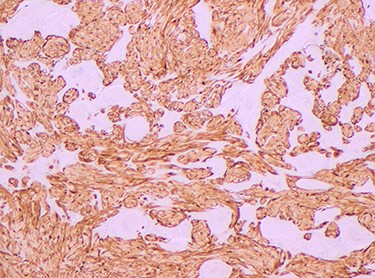

Histopathology of the right hemicolon found five firm nodules in the caecum and an additional seven polyps in the ascending colon macroscopically. Microscopically, a total of eight lesions in the caecum and ascending colon were found to be GCTs, varying in size from 1 to 7 mm. They were submucosal with intact covering mucosa (Figs 1 and 2). Tumour cells had periodic acid-Schiff (PAS)-positive granular cytoplasm and small nucleoli (Fig. 3). Immunohistochemical staining was positive for S-100 (Fig. 4) and inhibin. Twenty-four lymph nodes identified showed no abnormality. Spindling was seen in some tumours in this case, but overall, there are less than three worrisome features, and as such, these GCTs were considered atypical. Other polypoid lesions identified included two hyperplastic polyps and a submucosal lipoma.

Histologically GCTs are characterized by plump neoplastic cells with abundant eosinophilic granular cytoplasm. Immunohistochemistry for neural markers, S-100 protein and NSE are diffusely positive, while other markers include inhibin, calretinin and nestin [2, 4]. Fanburg-Smith et al. [3] described microscopic criteria to predict malignant potential, where GCTs meeting three or more criteria were classified as histologically malignant.